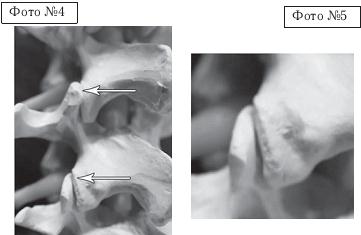

СКТ № 1

На спиральной компьютерной томографии (СКТ) № 1 наблюдается сращение между собой поперечных отростков LIII-LIV

СКТ № 2

На СКТ № 2 наблюдается аномальное слияние поперечногоотростка пятого поясничного позвонка с крестцом — сакрализация.